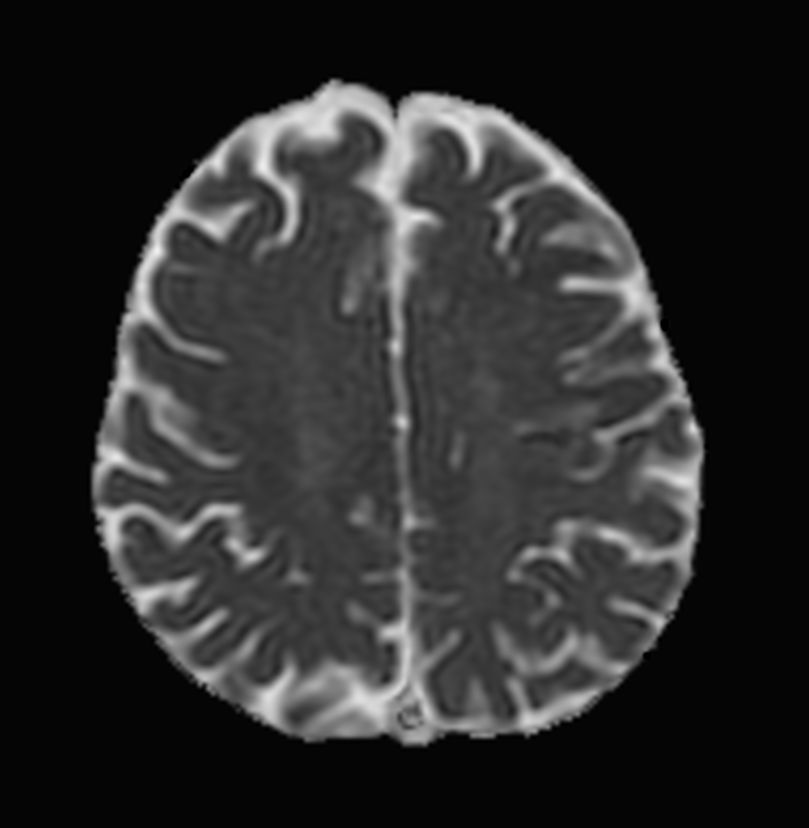

Patient with a small brain infarction. Compressed SENSE acceleration is used to speed up sequences while maintaining equal image quality. Three different diffusion methods are included; A fast 52 secs DWI EPI sequence, a high resolution DWI EPI sequence and a TSE based DWI sequence. A SWIp sequence is included offering high resolution 3D susceptibility weighted imaging to enhance contrast for deoxygenated (venous) blood or calcium deposits. 3D APT sequence is included providing contrast-free brain imaging, addressing the need for more confident diagnosis in brain neuro oncology by using the presence of endogenous cellular proteins to produce an MR signal. And a large FOV TOF MR Angiography sequence is included to check on brain vascular anatomy.

Axial DWI EPI (b1000)